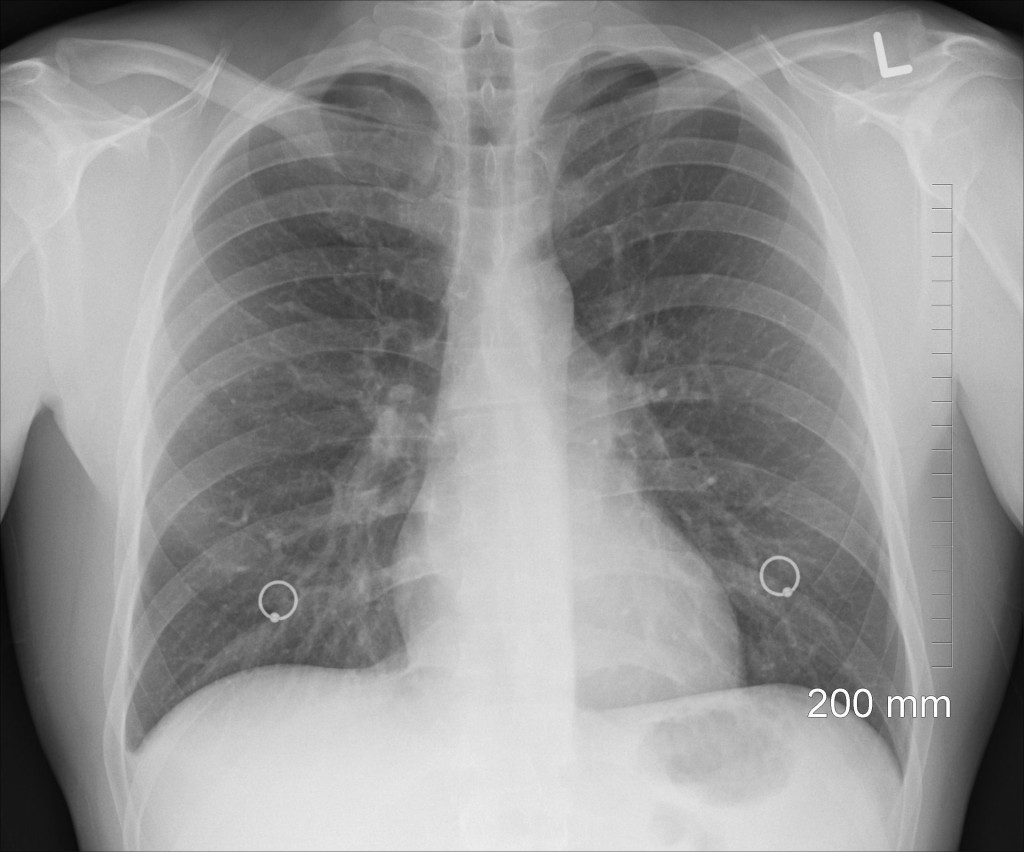

Longontsteking door protonpompremmers?

Over protonpompremmers bestaat observationeel onderzoek dat suggereert dat het gebruik ervan geassocieerd is met een grotere kans op longontsteking. Ook de NHG-Standaard Maagklachten maakt daar melding van, in verband waarmee chronisch gebruik wordt ontraden. Engelse onderzoekers gingen nu op…